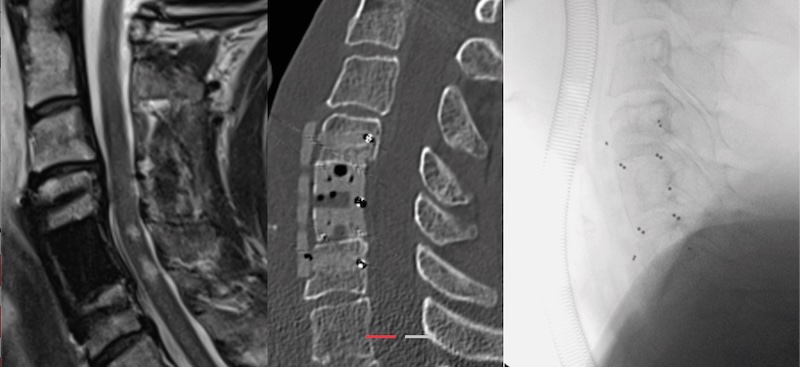

The Anterior Cervical Plate by icotec Medical is a metal-free ACP composed of radiolucent BlackArmor which is a proprietary carbon fiber reinforced PEEK material. The radiolucent nature allows for artifact free imaging post operatively. The plate features 1 to 4 levels and features carbon fiber/PEEK screws as well.

• Artifact-free post operative imaging